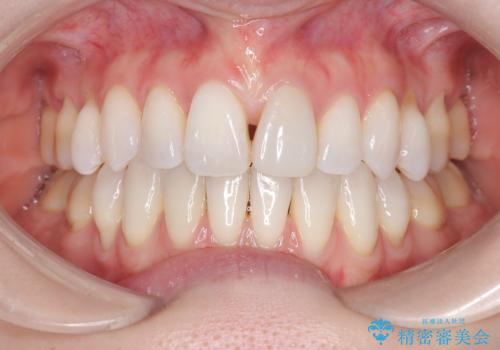

ハーフリンガル矯正|下顎前歯3本の特異症例を抜歯矯正で改善